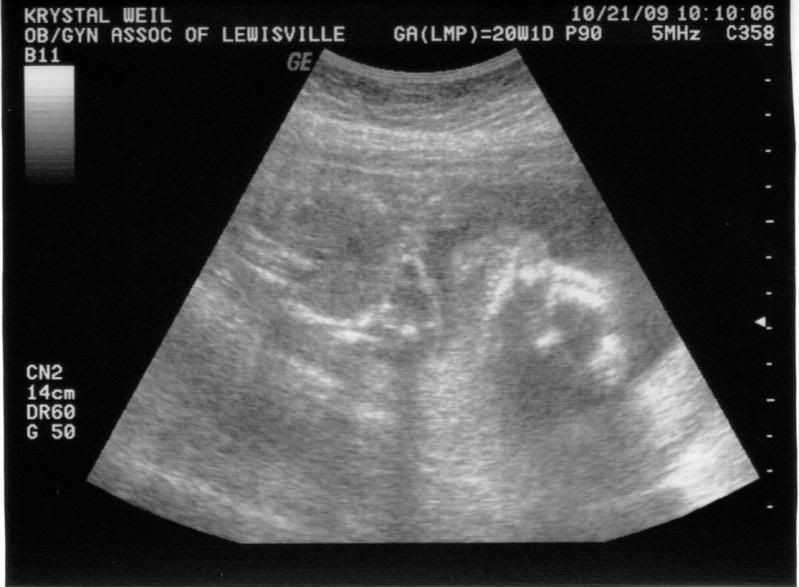

Here is a couple pictures from the ultrasound today. Enjoy!

Profile...